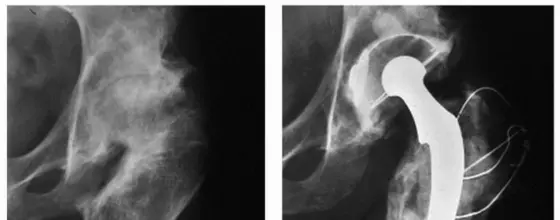

توضح هذه الصور حالة مريض يعاني من تشوه سابق في الفخذ القريب، حيث لم تسمح التقنيات الجراحية القديمة بتصحيح التشوه بشكل كامل، مما أدى إلى وضع مكون الفخذ في موضع غير مثالي وتسبب في ارتخاء الزرعة لاحقاً. هذا يؤكد أهمية التخطيط الدقيق والتقنيات الحديثة التي يتبعها الأستاذ الدكتور محمد هطيف.